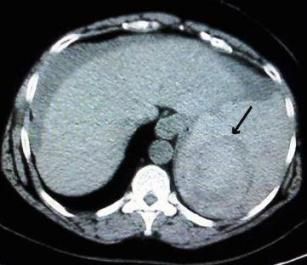

A 52-year-old obese woman presented to the emergency department for severe diffuse abdominal pain, nausea, and vomiting of 12 hours’ duration. She reported undergoing screening colonoscopy the day before.